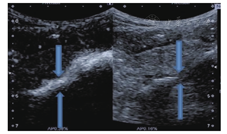

患者仰卧位或其他合适体位,在实时超声引导下确定穿刺点后常规消毒皮肤,铺无菌洞巾,再次确定穿刺点、穿刺途径和深度,2%利多卡因局部麻醉后进穿刺针,避开肠管和大血管沿引导线至腹腔脓肿处,拔出针芯,抽吸的脓液标本即送细菌培养及药敏试验检查,再插入导丝,开皮,置入引流管,接引流瓶,局部包扎,术后观察30 min,无不适可返回病房。一般需引流3~14 d,超声复查脓腔基本消失可拔除引流管。

置管引流术中需注意:(1)因脓腔内脓液浑浊,含坏死物、纤维块等物质,穿刺置管引流时宜首选口径较大的引流管。(2)选择合适路径,避开大血管和肠管,尤其对位置较深或盆腔的脓肿(盆腔脓腔与肛周脓肿相通时)可从肛周脓肿处置管,也能达到盆腔脓肿引流的目的。(3)对于多个分隔脓腔,可采用多点穿刺抽脓,使每个腔隙的脓液充分引流。(4)注意冲洗引流管,保持导管通畅,以便脓液顺利流出,引流不畅时可在超声引导下调整引流管位置。